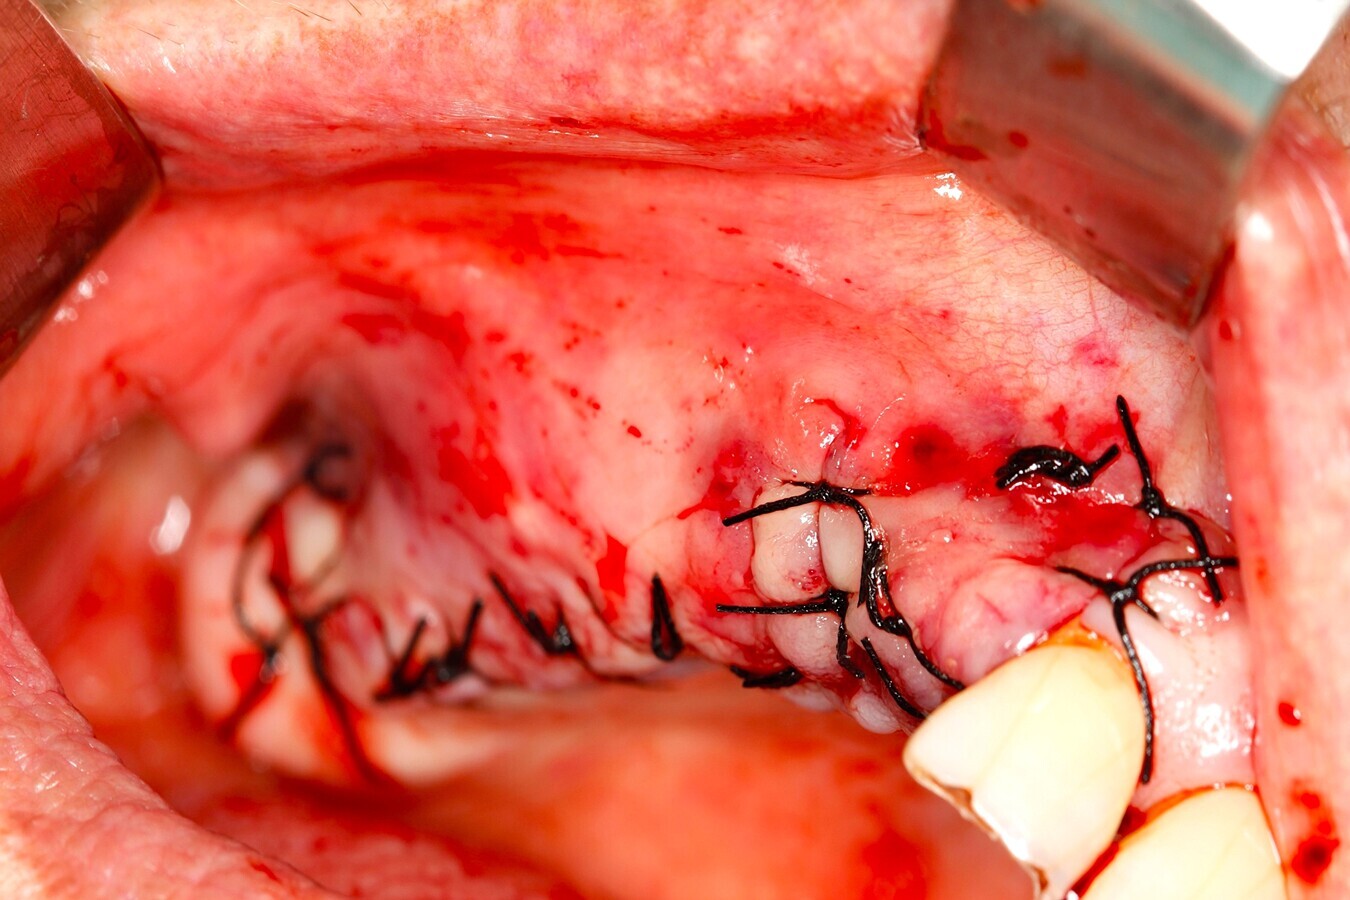

Fig. 18 Figura 18

9. Reposición del colgajo mucoperióstico, en caso necesario liberación del periostio para garantizar un colgajo sin tensión y cierre primario del lecho12.

10. Sutura de los colgajos con puntos simples y colchoneros horizontales con sutura de 4/013, 14.